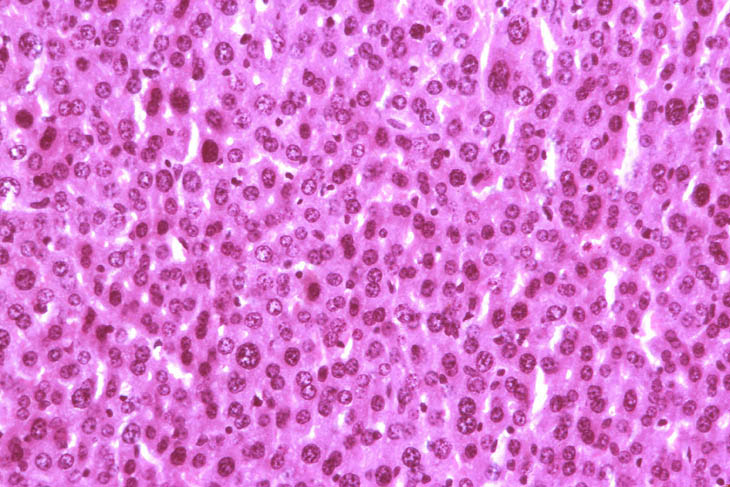

Hepatocyte atrophy and glycogen depletion after 90 days of exposure to malonaldehyde. Note paucity of cytoplasm and crowding of nuclei.